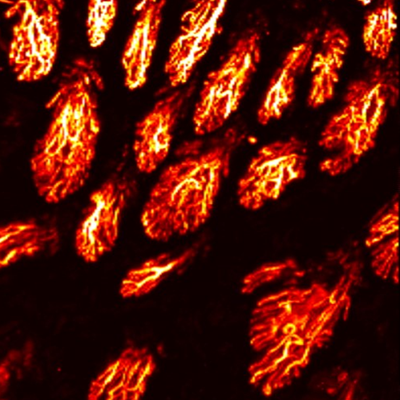

Layer by layer visualization of subdermal microvessels and pigments

MAP

Cross sectional view

Surface(Depth) view